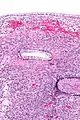

| Micrograph showing a mucinous cystadenoma of the ovary. H&E stain. | |

Mucinous cystadenoma is a benign cystic tumor lined by a mucinous epithelium. It is a type of cystic adenoma (cystadenoma).

Mucinous cystadenomas make up 15–20% of all ovarian tumors. They often become very large and can extend up into the abdomen.

Benign mucinous cystadenomas compose 80% of mucinous ovarian tumors[2] and 20–25% of benign ovarian tumors overall. The peak incidence occurs between 30 and 50 years of age. Benign tumors are bilateral in 5–10% of cases.

PRMC and benign mucinous cystadenoma of the ovary are microscopically similar. Both are multiloculated cystic neoplasms and are lined by a single layer of tall columnar cells with a clear basal nucleus and cytoplasm. Both of them have identical histochemical and ultrastructural features.[9] Flat to low cuboidal cells, resembling mesothelial cells, in the lining interspersed between columnar cells in the same area is the only histological difference between the two tumors.[9]